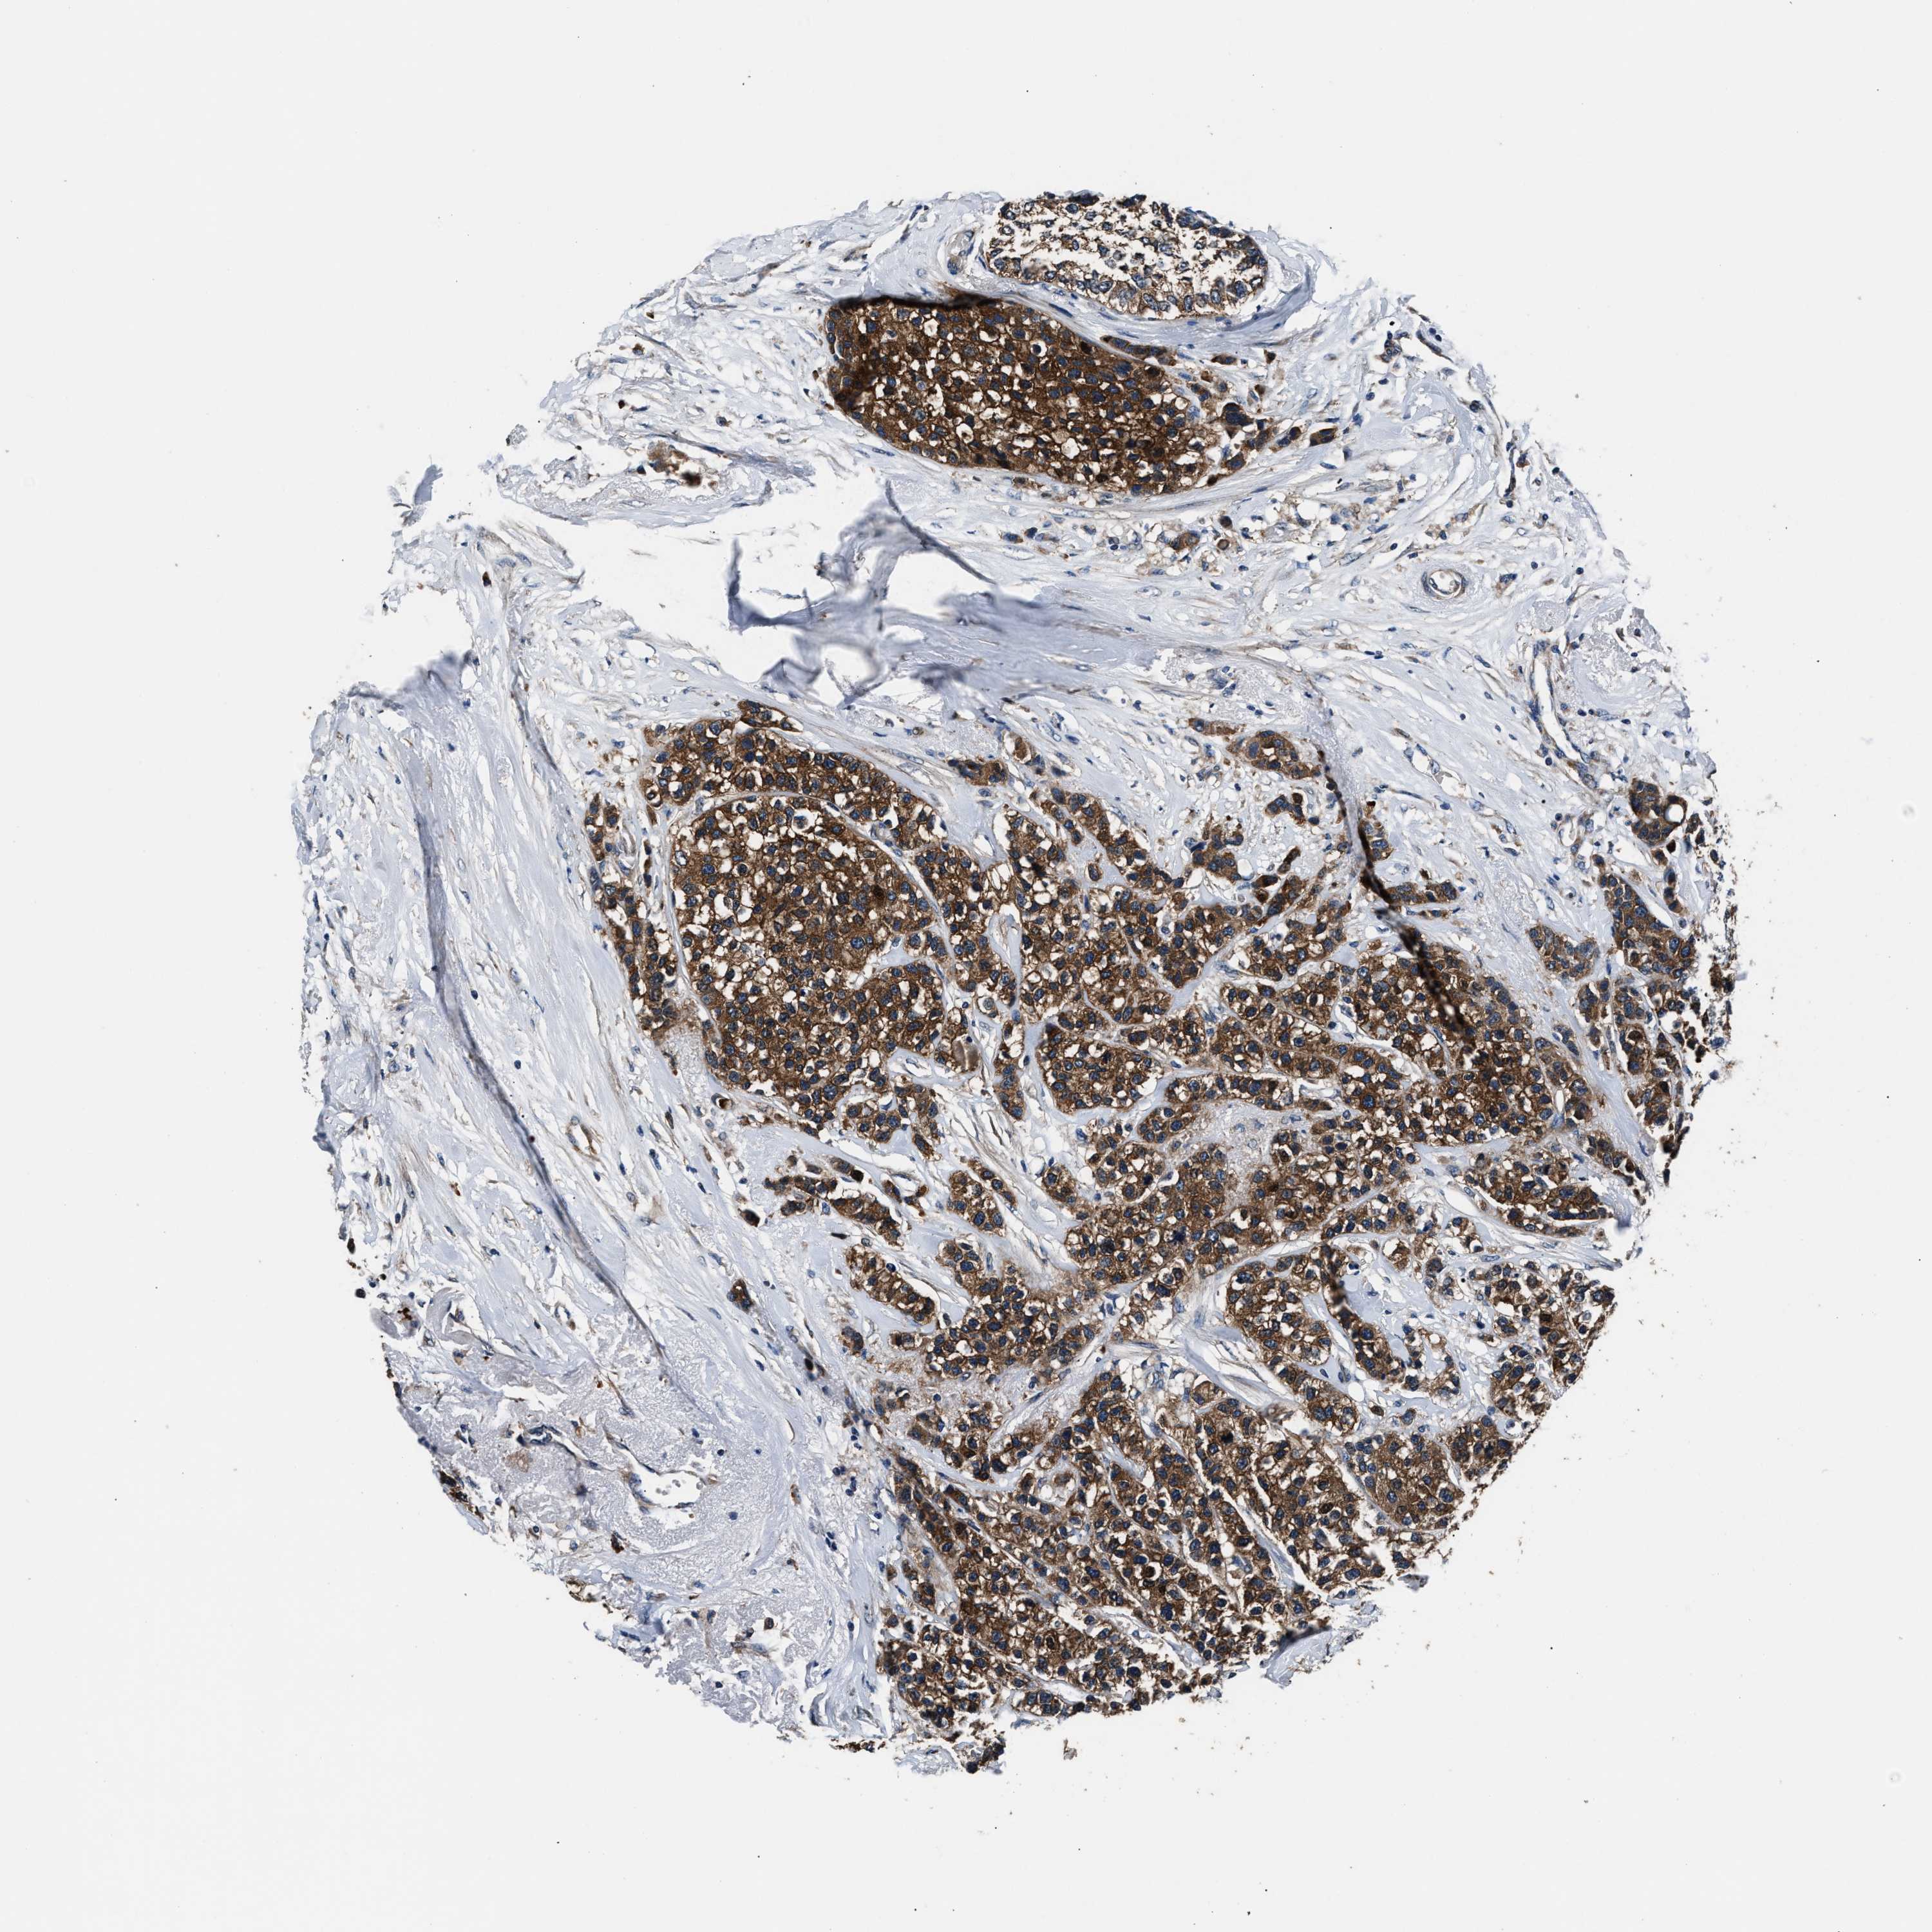

CANCER BREAST CANCER Show tissue menu

BRCA TCGA BRCA VALIDATION PROTEIN EXPRESSION

Breast cancer

Human cancer

Breast invasive carcinoma